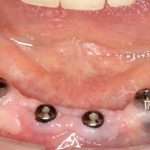

Простой пример. Возьмём один и тот же клинический случай — полную потерю зубов вследствие удаления на одной из челюстей. Что-то типа этого:

И вот представьте, что с подобной клинической картиной обращаются два человека.

Второй пациент — 80-летняя бабушка, большую часть своей жизни пользующаяся полным съёмным протезом. Какие имплантологические решения мы им предложим и от чего они будут зависеть? Ведь вариантов достаточно много.

80-летняя бабушка жалуется на то, что у неё съемный протез выпадает, ей перед подругами по лавочке стыдно. И она ожидает, что мы придумаем какую-нибудь штуку, которая поможет её протезу держаться на челюсти и не выпадать.

Скажите, каким будет оптимальное решение в её случае? 2 импланта, шариковые абатменты или локаторы:

Просто фиксируем существующий протез к имплантам — и всё! Бабушка счастлива!